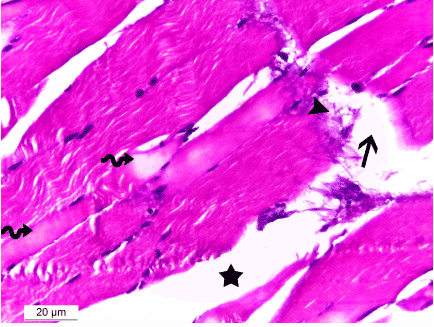

| Figure 5: Photomicrograph of a section in skeletal muscle of a rat of group II showing: wide separation of the skeletal myocytes (star), fragmentation (arrowhead) and marked disruption (arrow) of the skeletal muscle fibers. Some muscle fibers showed areas of hyalinization of the sarcoplasm (wavy arrows). Hx& E 400x. |